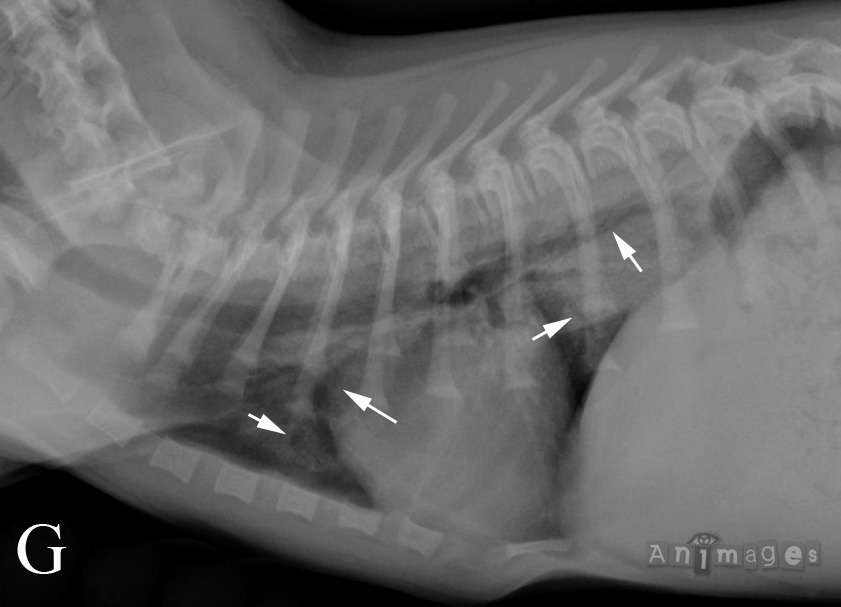

Latérale gauche